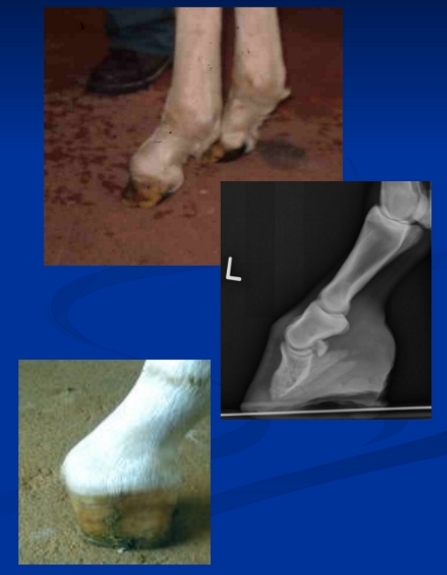

Pastern dermatitis (scratches/grease heel)

Et: Chronic painful dermatitis of pastern/heel bulbs from mud/wetness, Staph, Dermatophilus, fungi, mites

Cs: dry/Crusting, alopecia, ulceration, swelling, pain

Dt: Clinical eval, skin scraping, biopsy

Tx: remove from mud/wetness, Soak, clip, topically with antifungals, steroids, antibiotics, ivermectins, time